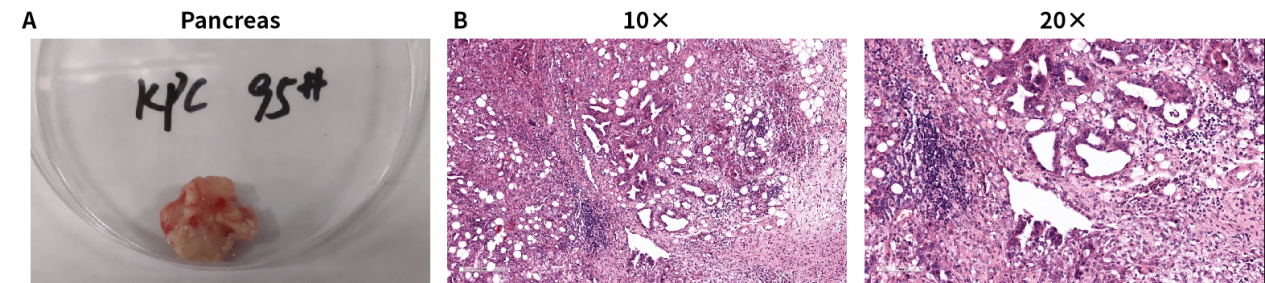

KPC小鼠是目前成功建立的一种胰腺导管腺癌模型小鼠,具有很多与人胰腺癌相似的特点,如胰腺内皮细胞瘤形成,强烈的免疫反应等。80%的KPC小鼠出现了肝转移和肺转移的现象。KPC小鼠包含了KRAS和TP53基因突变,而在人胰腺癌的研究中发现,分别有80%和70%的患者表达这两种突变蛋白。 KPC小鼠的P53基因含有一个显性抑制性点突变( TP53R172H ),KRAS基因含有一个条件性活化点突变(KRASG12D)。KRAS突变基因的上游含有lox-stop-lox终止序列,其在没有cre重组酶的条件下是不表达的。将Cre重组酶连接到PDX1的启动子后,其将在胰腺的腺泡、胰岛和导管中表达。

验证数据:

小鼠组织病理学检测:

图1 KPC小鼠模型的自发式性胰腺癌体和HE染色结果。胰腺表面不平整,多个结节状突起;细胞排列无序,组织结构呈不规则细胞团,可见胰腺导管增生,炎症细胞浸润,间质纤维形成,符合肿瘤组织结构特征。